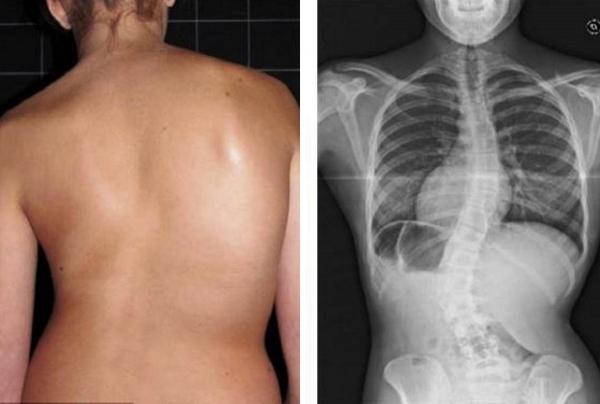

Lihat foto-foto ini. Inilah yang terjadi pada mereka yang tidak memperhatikan gejala. Hari ini, mereka adalah orang-orang yang tak berdaya, dan banyak di antara mereka tidak memiliki siapa pun untuk membantu. Apakah Anda menginginkan nasib seperti itu?

"Punggung bungkuk janda" — deformasi tulang belakang yang menyebabkan nyeri tak tertahankan yang semakin memburuk setiap hari.

Hernia cakram tulang belakang, kompresi saraf, kehilangan sensasi, dan kelumpuhan parsial pada kaki.